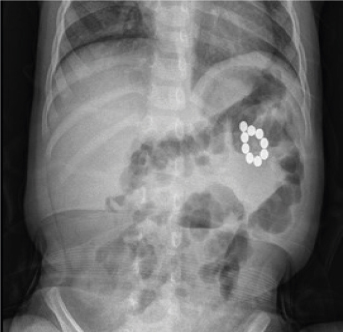

A 2-year-old boy presented with abdominal pain and bilious vomiting for 6 days. He had a fever for 3 days. He ingested multiple bead-shaped magnetic toys. On admission, he had abdominal pain and mild fever (body temperature, 37.5°C). His abdomen was soft, mildly tender, and not distended on physical examination. Laboratory findings were normal. Abdominal radiography revealed no free air and 11 bead-shaped magnets arranged in a circle (Fig. 1). Serial radiographs were followed up for 2 days. They showed no significant change in the position of the magnets, and the abdominal pain did not improve. Therefore, exploratory laparotomy was performed. Multiple perforations of the jejunum caused by the loops of magnets were found approximately 15 and 35 cm distal to the Treitz ligament. It was not appropriate to perform primary repair because there are too many perforation sites in the short bowel loop and discoloration was observed. Twenty-five cm of the jejunum, including all 5 perforation sites, was resected, and a primary anastomosis was made (Fig. 2). He had an uneventful postoperative recovery course and was discharged on the fifth postoperative day.

Fig. 1

Abdominal X-ray demonstrating 11 bead-shaped magnets in mid abdomen.